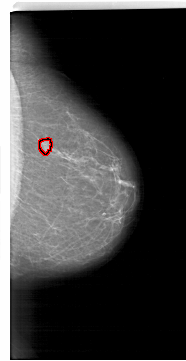

A_1718_1.RIGHT_MLO

LEFT_MLO LINES 6241 PIXELS_PER_LINE 3166 BITS_PER_PIXEL 12 RESOLUTION 43.5 NON_OVERLAY

FILE: A_1718_1.RIGHT_MLO.OVERLAY

TOTAL_ABNORMALITIES 1

ABNORMALITY 1

LESION_TYPE MASS SHAPE FOCAL_ASYMMETRIC_DENSITY MARGINS ILL_DEFINED

ASSESSMENT 4

SUBTLETY 4

PATHOLOGY BENIGN

TOTAL_OUTLINES 1

BOUNDARY